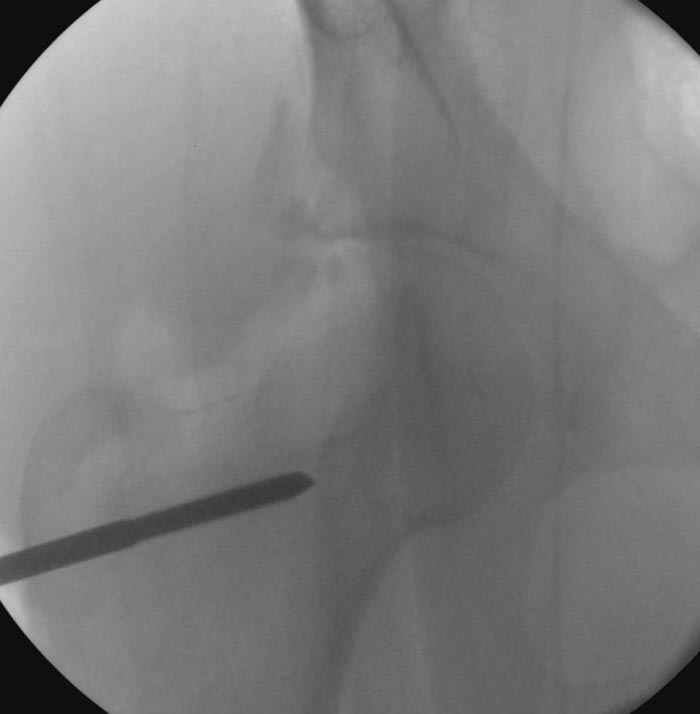

5:24 Рентгенограмма таза, вызывают врача ортопеда (снимок N1), его диагноз: закрытый переломо-вывих правого тазабедренного сустава, получает добро на закрытую репозицию в приемном отделении

5:38 Дважды неудачная попытка закрытой репозиции в приемном отделении

N 2